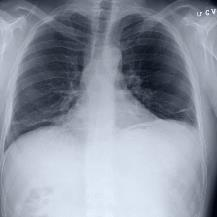

Thoracic disease detection from chest radiographs using deep learning methods has been an active area of research in the last decade. Most previous methods attempt to focus on the diseased organs of the image by identifying spatial regions responsible for significant contributions to the model's prediction. In contrast, expert radiologists first locate the prominent anatomical structures before determining if those regions are anomalous. Therefore, integrating anatomical knowledge within deep learning models could bring substantial improvement in automatic disease classification. This work proposes an anatomy-aware attention-based architecture named Anatomy X-Net, that prioritizes the spatial features guided by the pre-identified anatomy regions. We leverage a semi-supervised learning method using the JSRT dataset containing organ-level annotation to obtain the anatomical segmentation masks (for lungs and heart) for the NIH and CheXpert datasets. The proposed Anatomy X-Net uses the pre-trained DenseNet-121 as the backbone network with two corresponding structured modules, the Anatomy Aware Attention (AAA) and Probabilistic Weighted Average Pooling (PWAP), in a cohesive framework for anatomical attention learning. Our proposed method sets new state-of-the-art performance on the official NIH test set with an AUC score of 0.8439, proving the efficacy of utilizing the anatomy segmentation knowledge to improve the thoracic disease classification. Furthermore, the Anatomy X-Net yields an averaged AUC of 0.9020 on the Stanford CheXpert dataset, improving on existing methods that demonstrate the generalizability of the proposed framework.